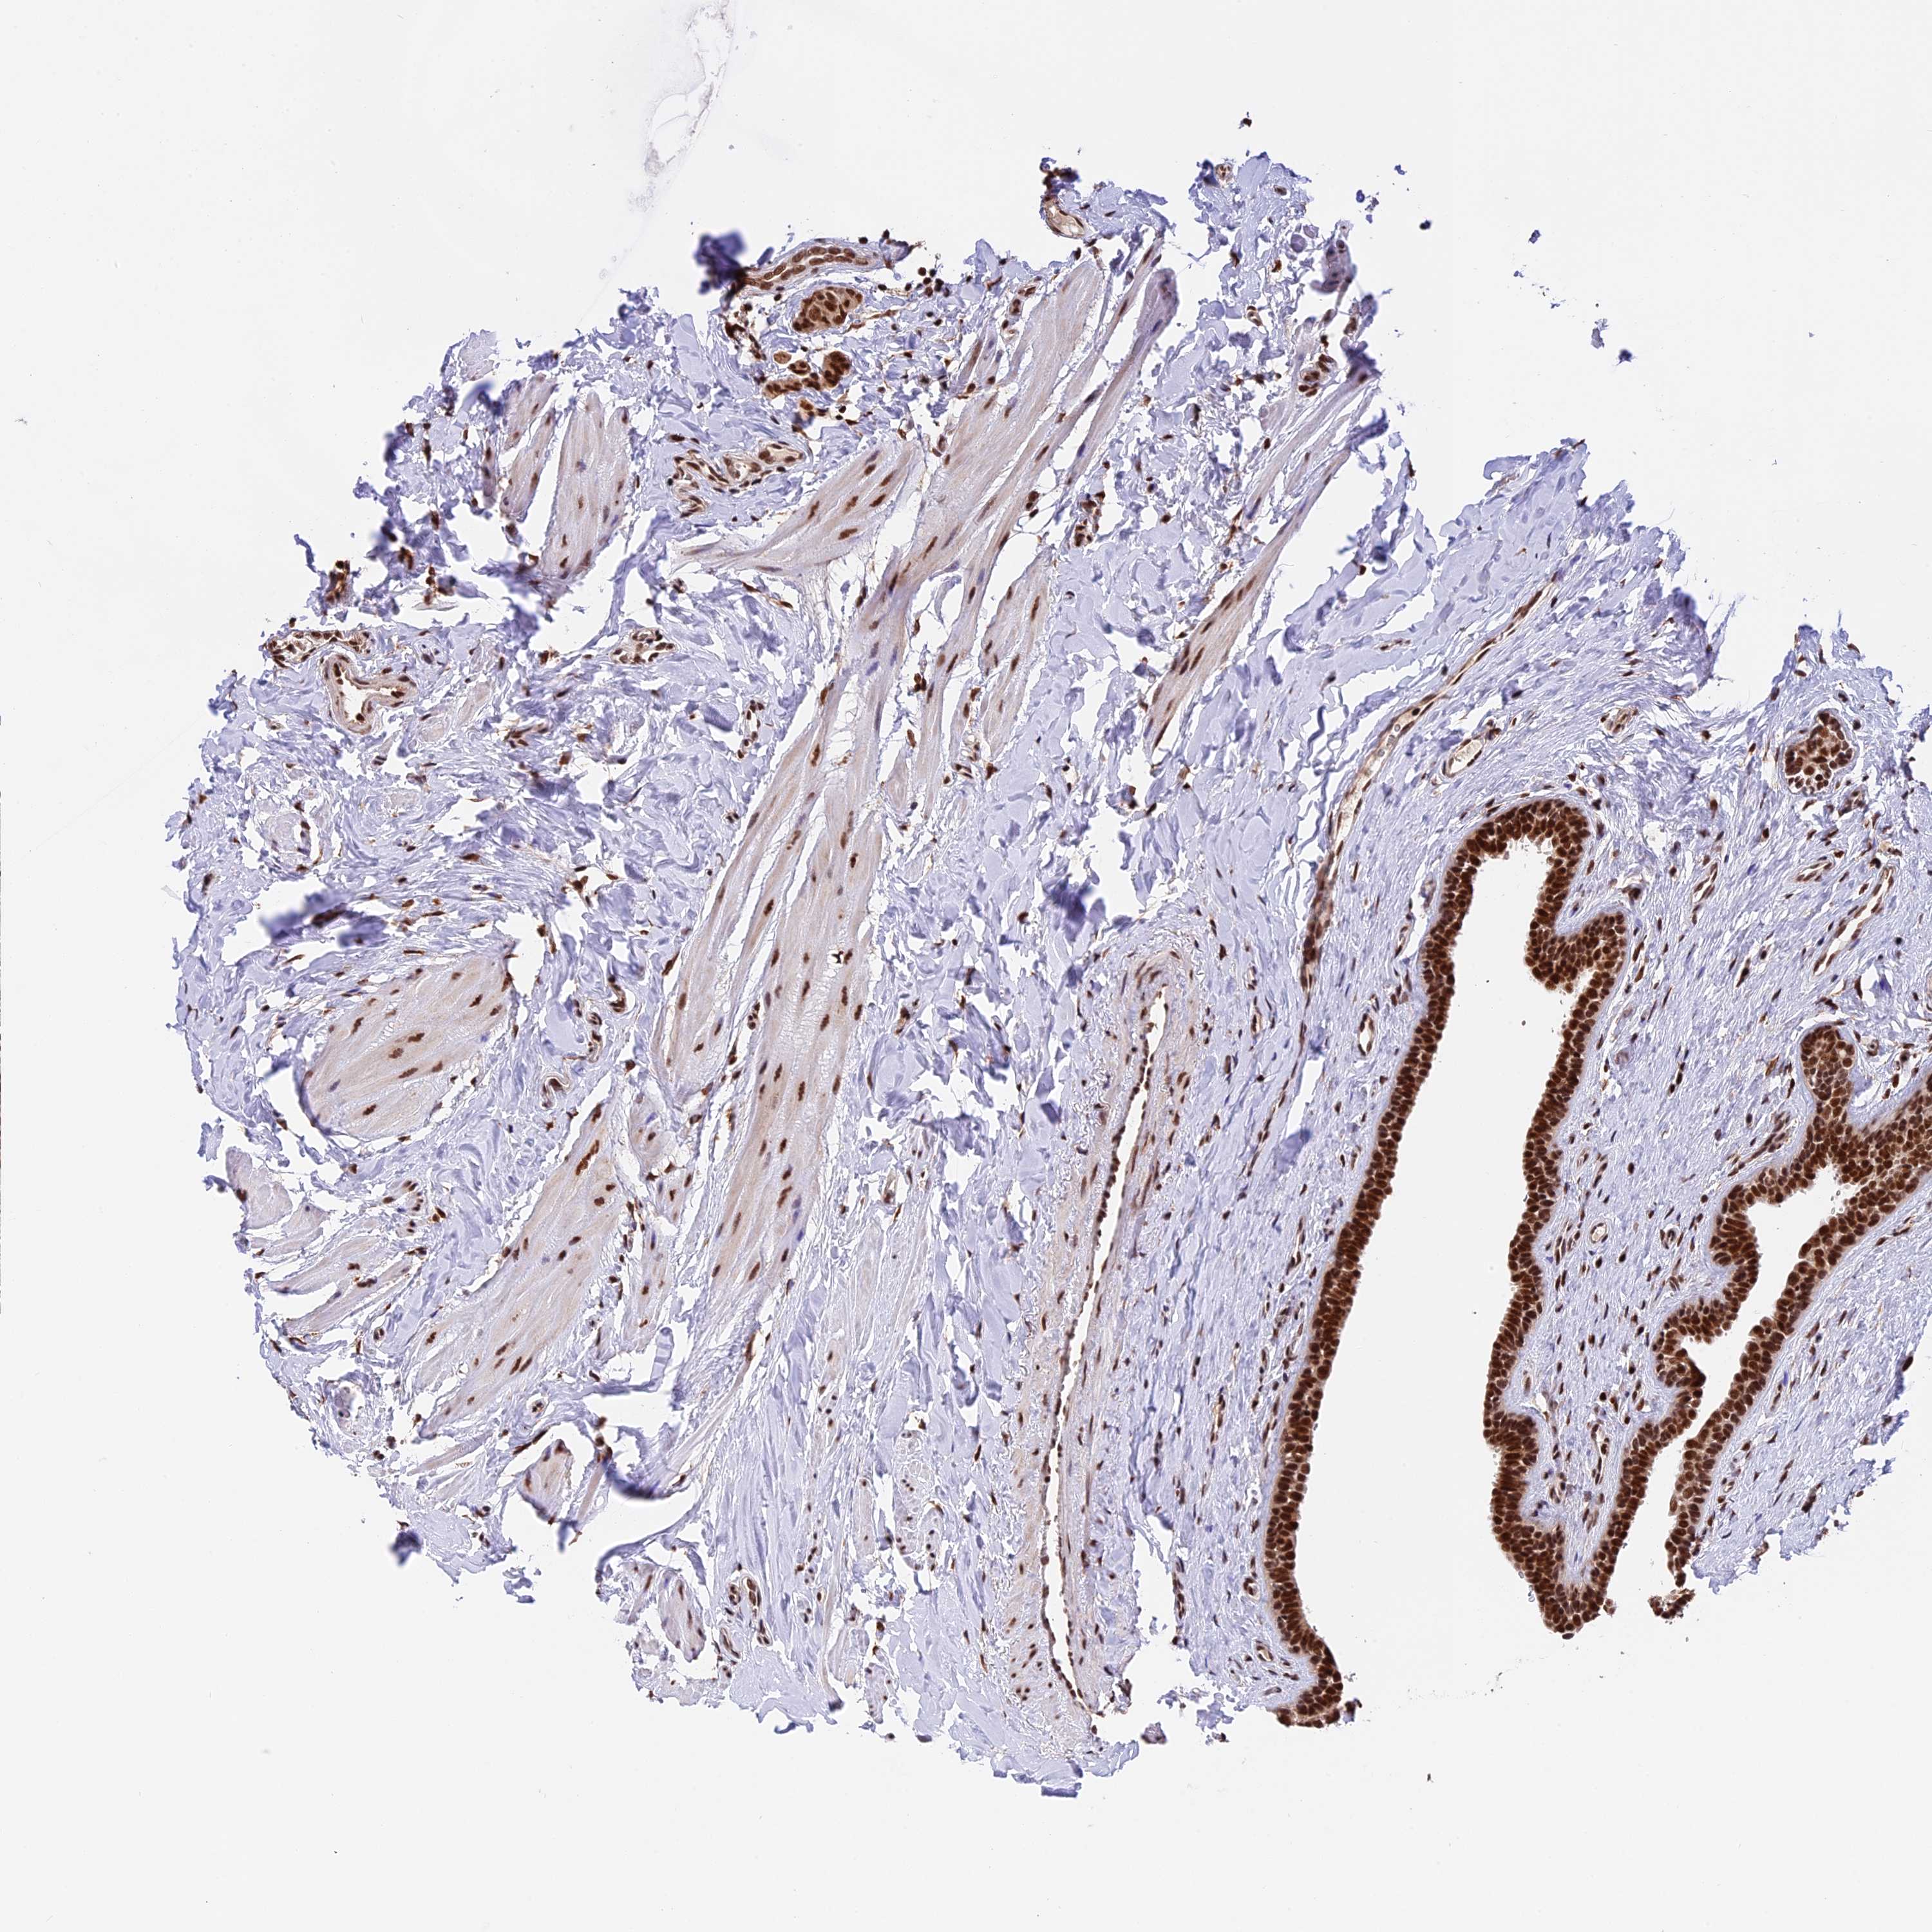

BRCA TCGA BRCA VALIDATION PROTEIN EXPRESSION